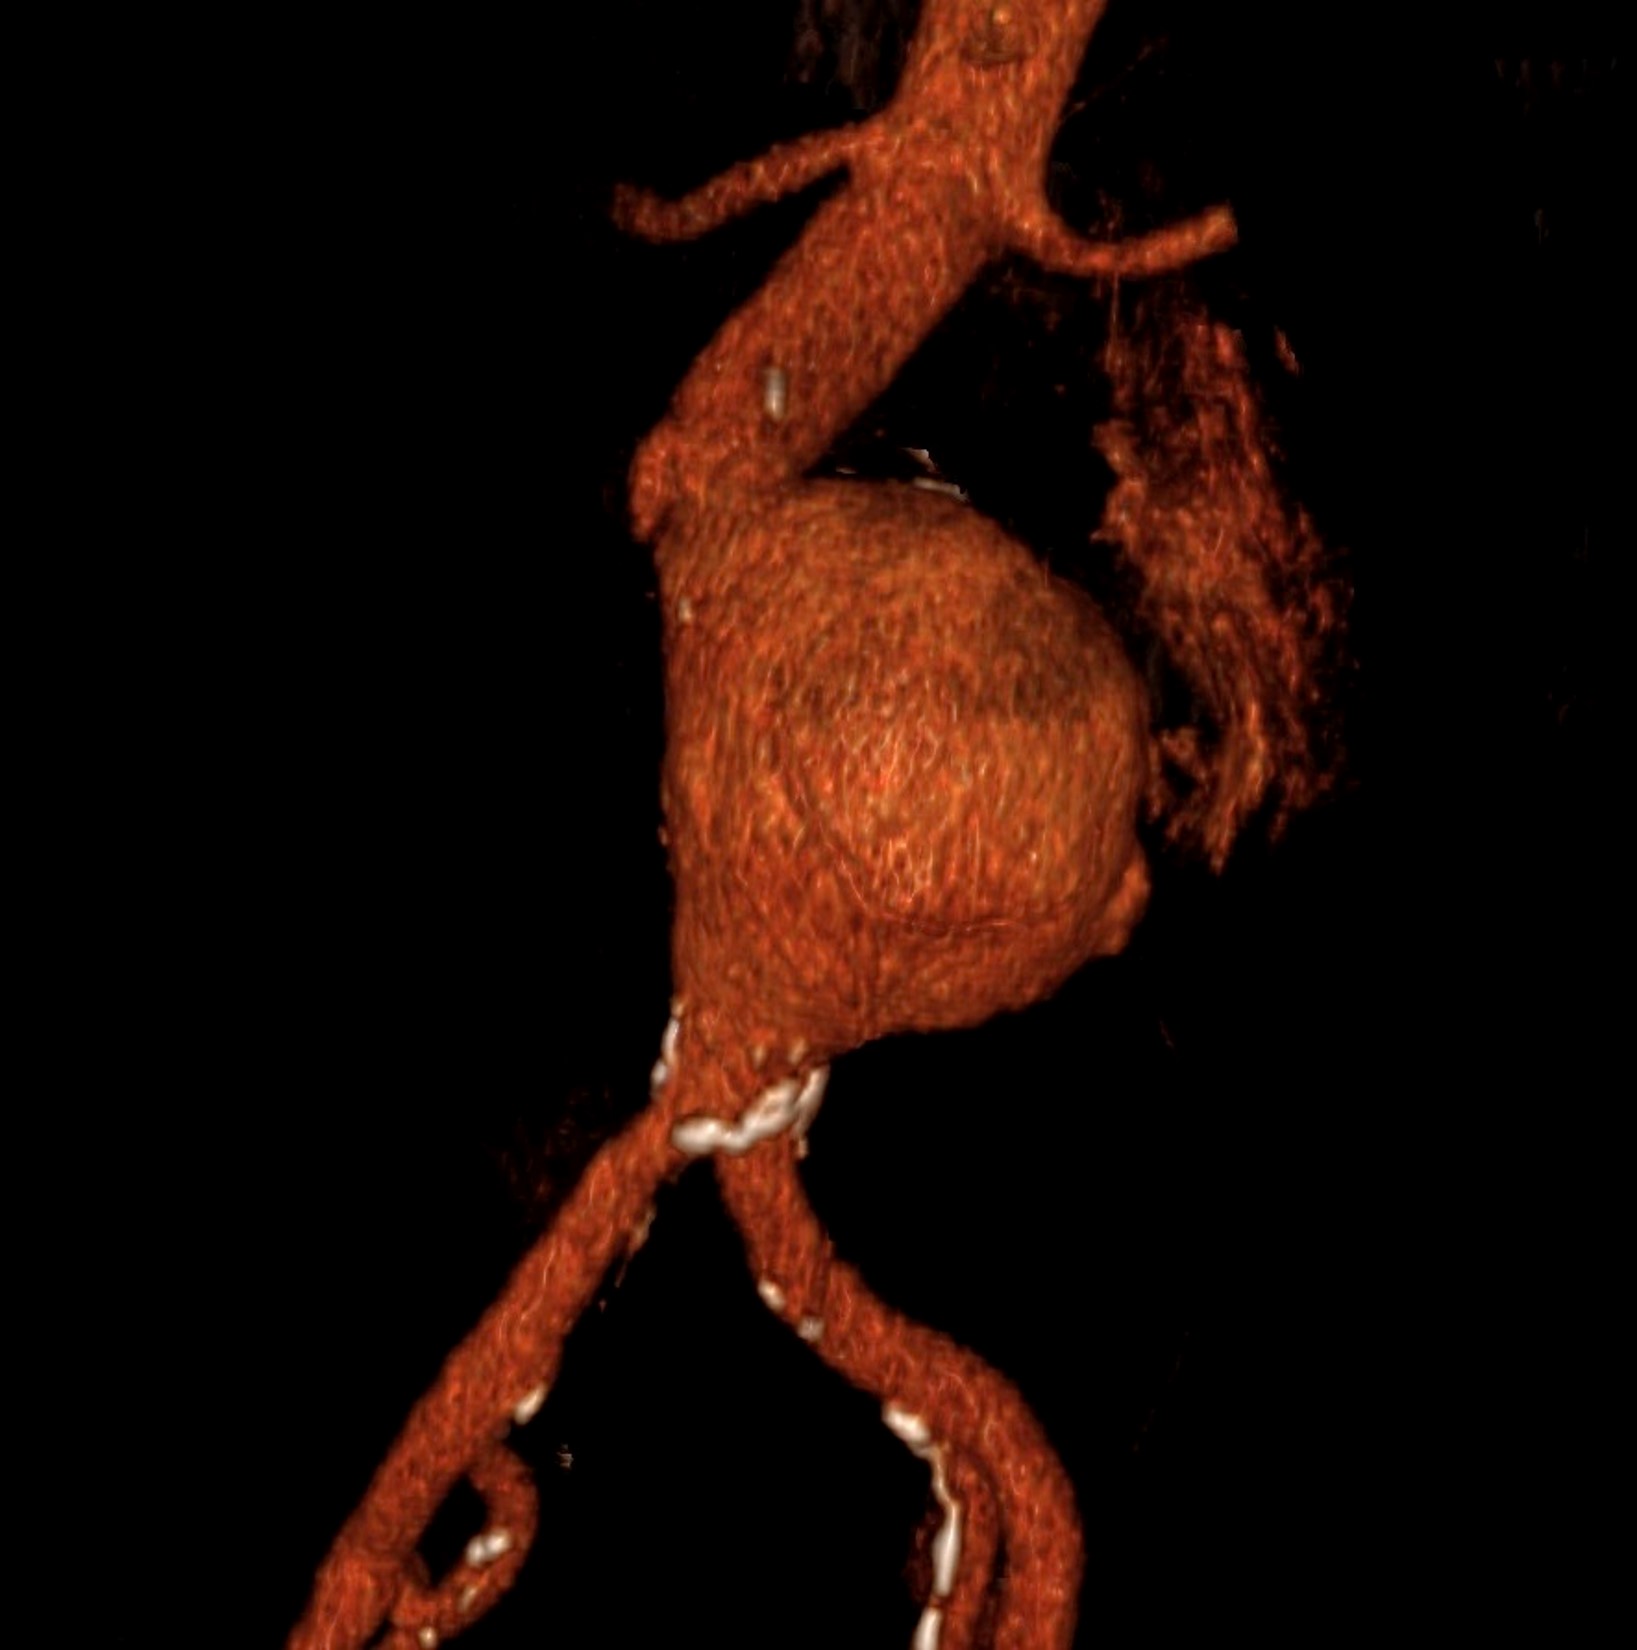

Ανεύρυσμα κοιλιακής αορτής

Ένα αορτικό ανεύρυσμα εντοπίζεται συχνά στην κοιλιακή χώρα, το λεγόμενο ανεύρυσμα κοιλιακής αορτής, και συνήθως θεωρείται ότι υπάρχει όταν υπερβαίνει τα 30 χιλιοστά. Οι αορτές με μέγεθος 25-29 χιλιοστά πρέπει να θεωρούνται εκκολαπτόμενα ανευρύσματα

Συνεχόμενη διαστολή και ρήξη. Η ταχύτητα διαστολής καθώς και ο κίνδυνος ρήξης καθορίζεται κυρίως από το μέγεθος (διάμετρος) του ανευρύσματος, αλλά υπάρχουν και μεγάλες επιμέρους παραλλαγές. Σε γενικές γραμμές ένα ανεύρυσμα κάτω από 5,0–5,5 εκατοστά σπάνια σπάει.

Χειρουργική προληπτική επέμβαση, ανώδυνη και σχεδόν αναίμακτη

✓ Διαδερμική τοποθέτηση συνθετικής αορτής – μοσχεύματος σε ειδική χειρουργική αίθουσα με αγγειογράφο